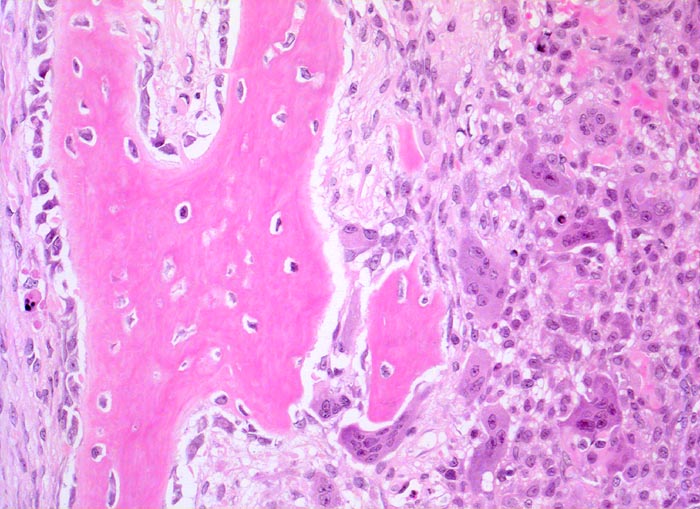

aneurysmatische Knochenzyste (AKZ)

Knochen, Fibula

Neugebildeter Faserknochen mit Osteoblasttapete. Daneben dichtliegende mononukleäre Zellen und mehrkernige Riesenzellen. Streifenförmige besenreiserartige Matrixbildung.

Lokalisierte Schmerzen und Schwellung in der proximalen Fibula. Im Röntgenbild ist eine Osteolyse erkennbar, die die betroffene Fibula auftreibt. Die Cortikalis über der Osteolyse ist hauchdünn.

200